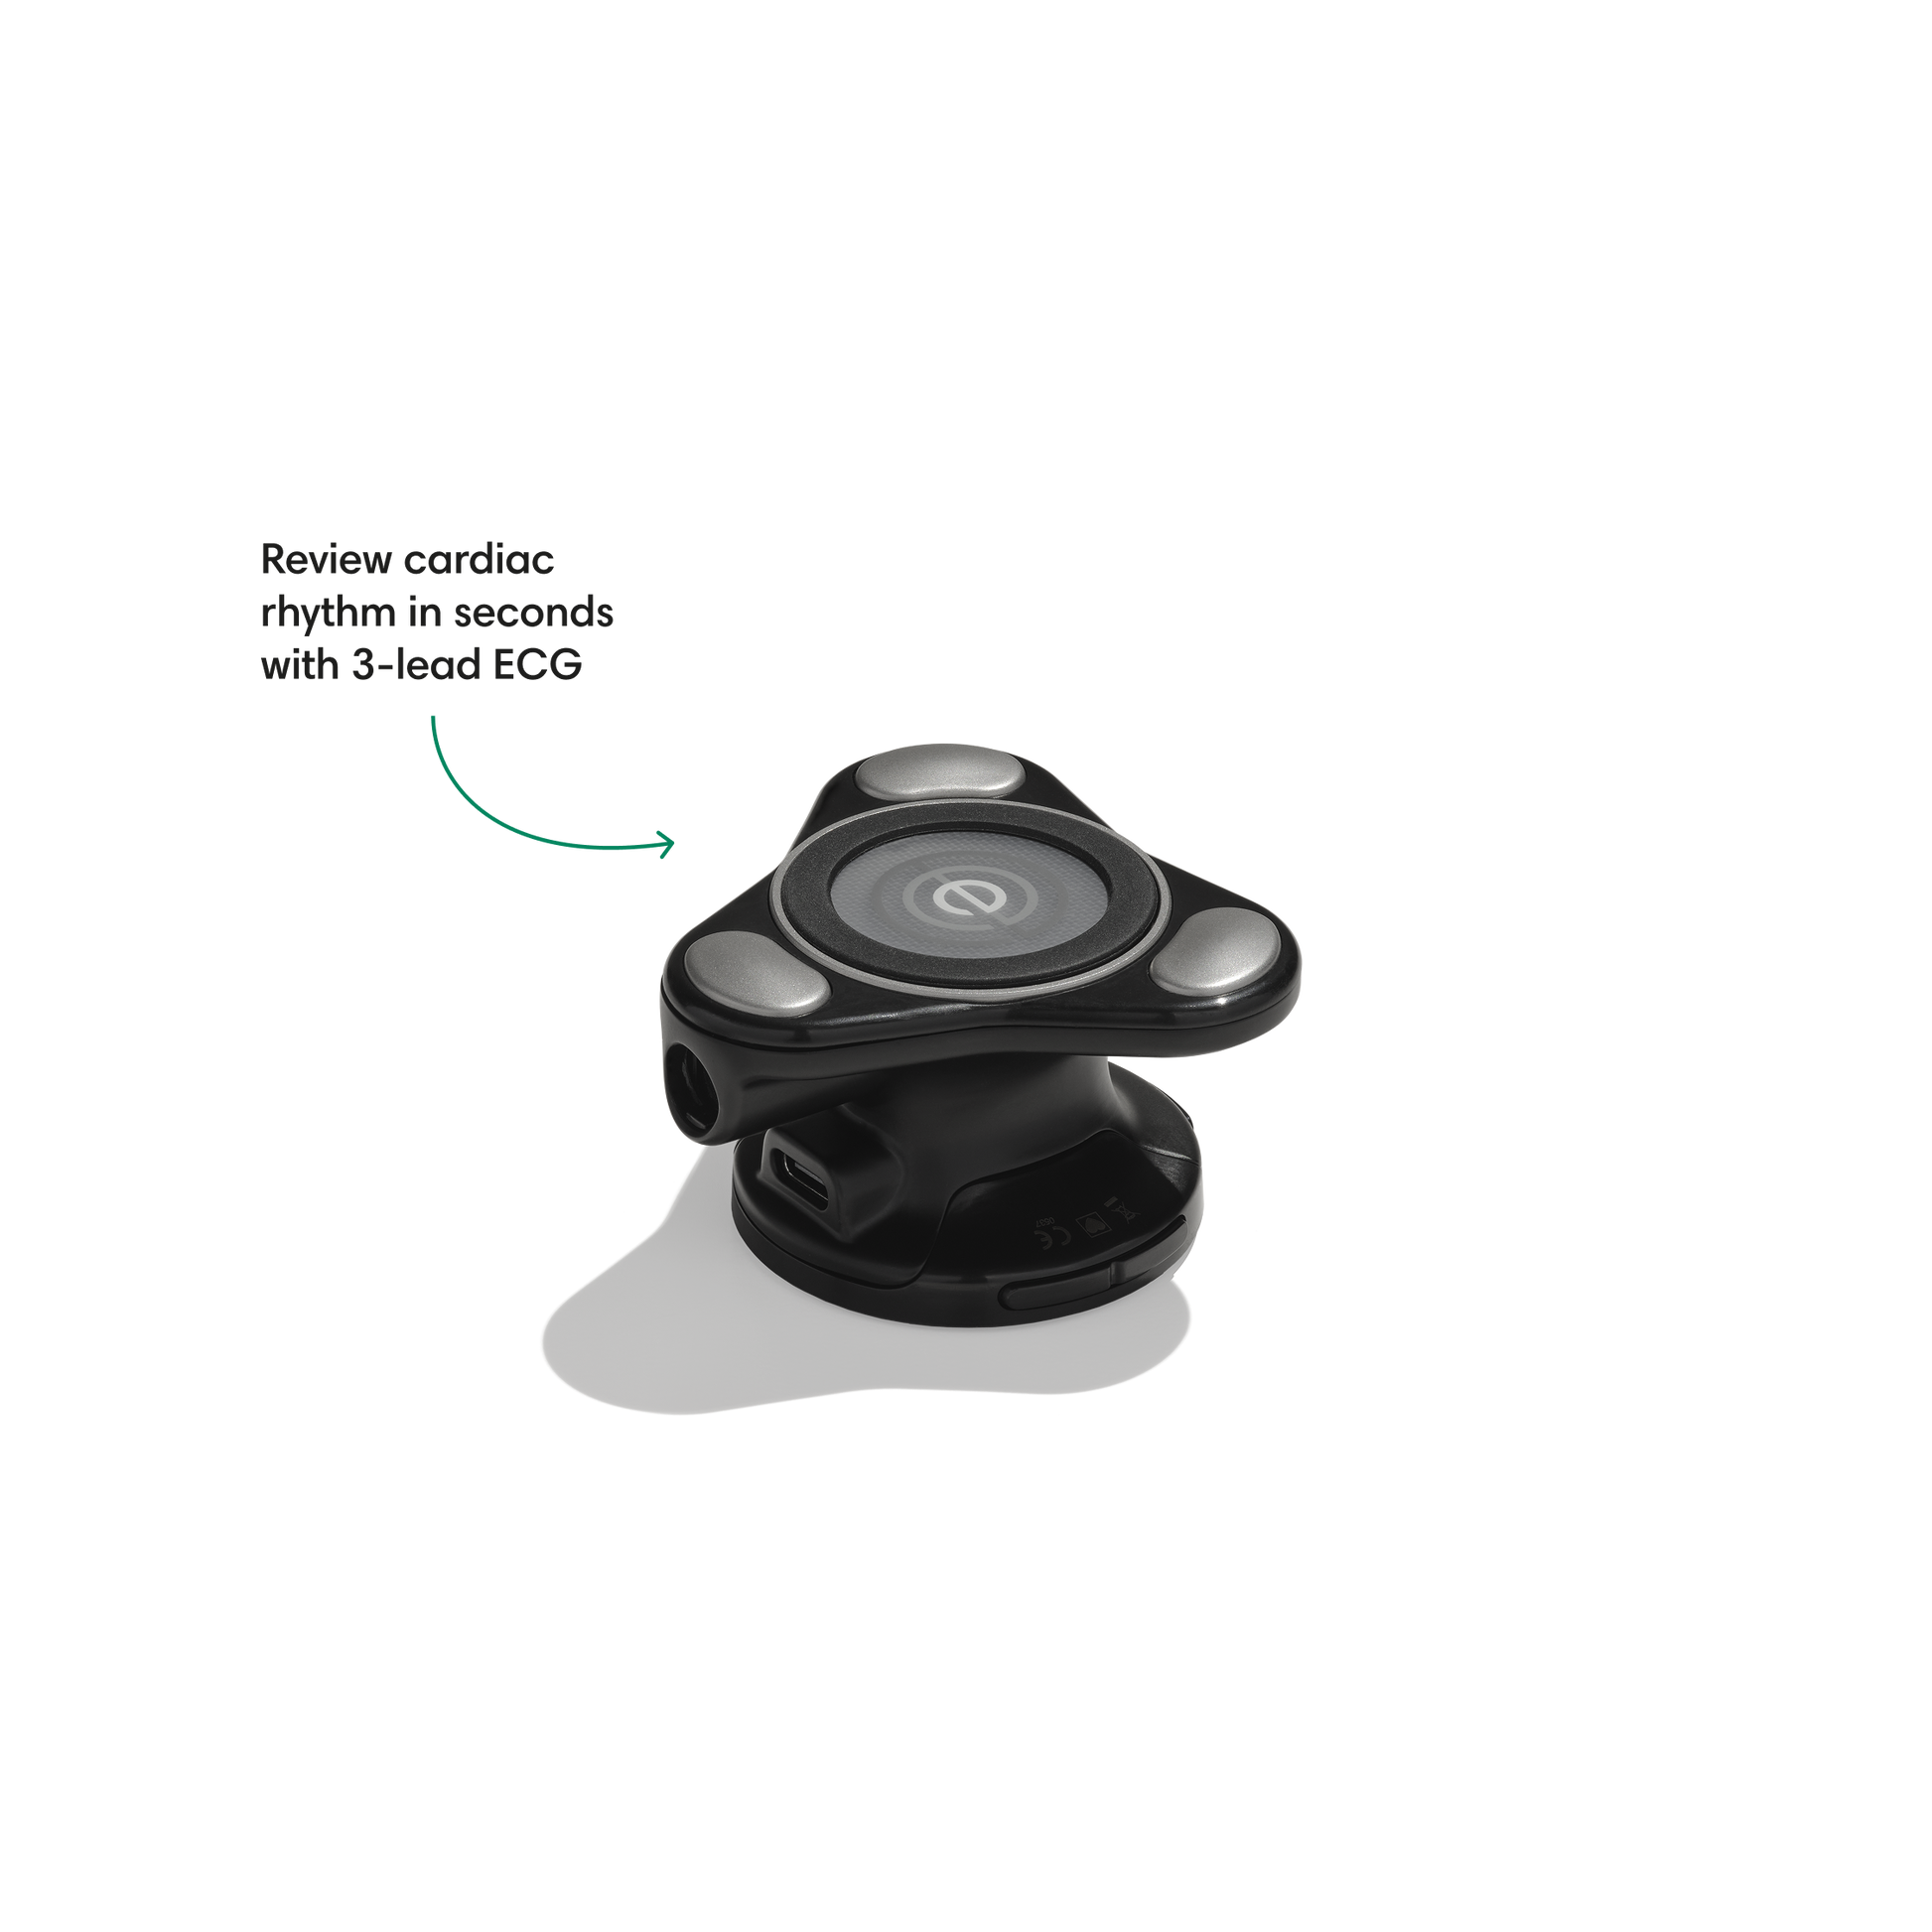

Go beyond sound alone.

For the first time ever, measure heart rate, visualize 3-lead ECG, and see detection results — right on a built-in, full-color display.